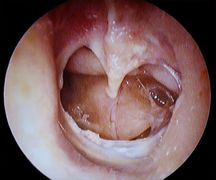

Ear

Mastoiditis with subperiostal abscess

Mild otitis externa

Severe otitis externa